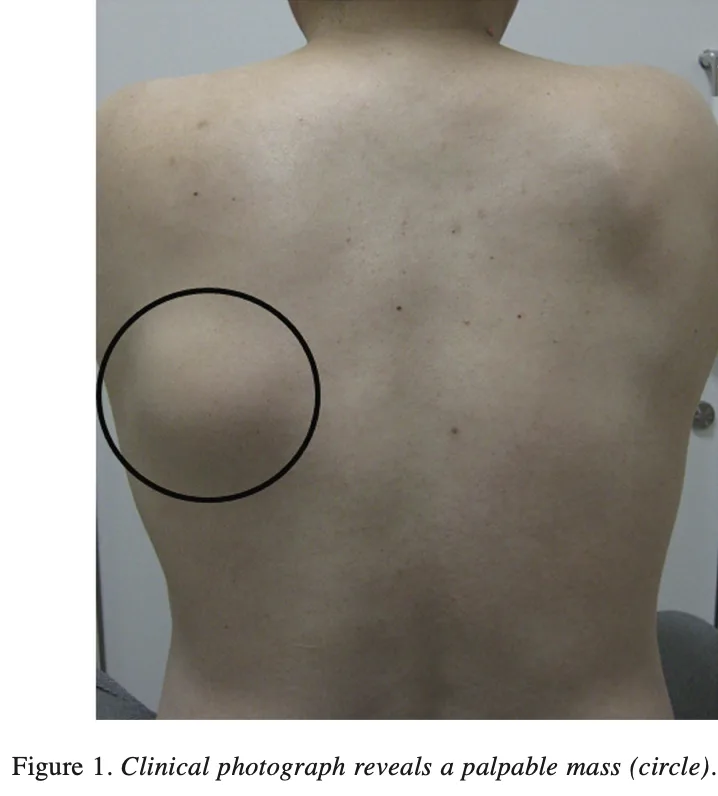

他科に通院中の後期高齢患者さんが, 背中に腫瘤があるため, 当科に紹介されました.

肩甲骨の下方内側に腫瘤があります.

肩甲骨の下寄りのすぐ内側に5 cm弱の腫瘤がありました.